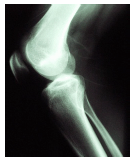

A questão a seguir, estão relacionadas com a imagem radiográfica abaixo:

A partir da anatomia radiológica demonstrada nessa imagem, é CORRETO afirmar que se trata da incidência